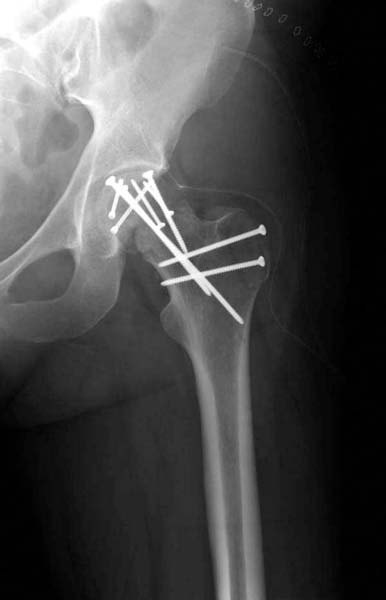

Трудно выбрать приоритет, когда имеется одинаковые по значимости, по сложности повреждения и с вовлечением различной локализации. У пожилых переломо-вывих головки бедра можно было бы проигнорировать, но у молодых такое решение привело бы к катастрофе, и поэтому приоритет первичной фиксации отдали решению переломо-вывиха таранной кости и головки бедра.

Больная стабильная после хирургических мероприятии и получив добро, приступили к закрытому вправлению таранной кости с укладкой наружного фиксатора. Затем укладка больную на бок и открытый остеосинтез перелома-вывиха головки бедра.

По характеру повреждения головка находится сзади и напрашивается задний Кохер-Лангенбек доступ, но в заднем доступе имеется риск повреждения магистрального кровоснабжения головки a. circumflexa. Более щадящая trochanteric flip (digastric osteotomy) сохранит кровоснабжение и дасть возможность работу при вывихнутом суставе.

После спадения отека на стопе произведена фиксация тарана. Кстати, коллеги пересмотрели первоначальную консультацию по позвоночнику и на двух уровнях провели фиксацию. Из-за длительного постельного режима без нагрузки таз не стали оперировать...